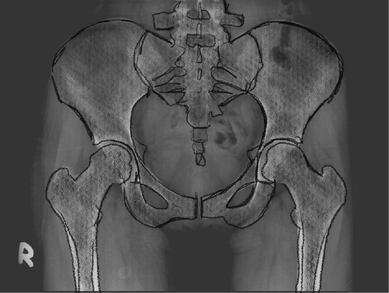

Total hip replacement

Regain your mobility and live pain-free with advanced robotic hip replacement surgery, designed for precision and faster recovery.